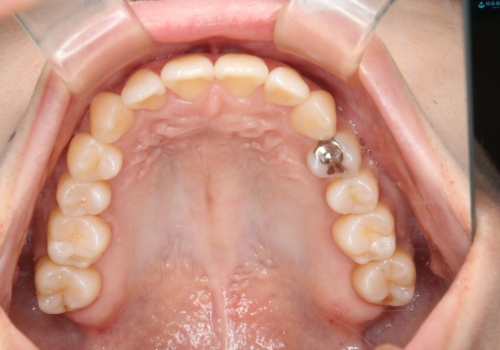

- 上の前歯は内側に入っていることが気になりご相談にいらした方です。インビザラインにて治療を行いました。

1週間でのマウスピース交換を指示していましたが、20時間以上使えない時があると不安との事で、2週間ごとの交換にしていました(実際はほとんど20時間以上使用できていたようです)。治療終了まで時間はかかりましたが、最終的に綺麗に並べることができ、大変喜んでいただけました。